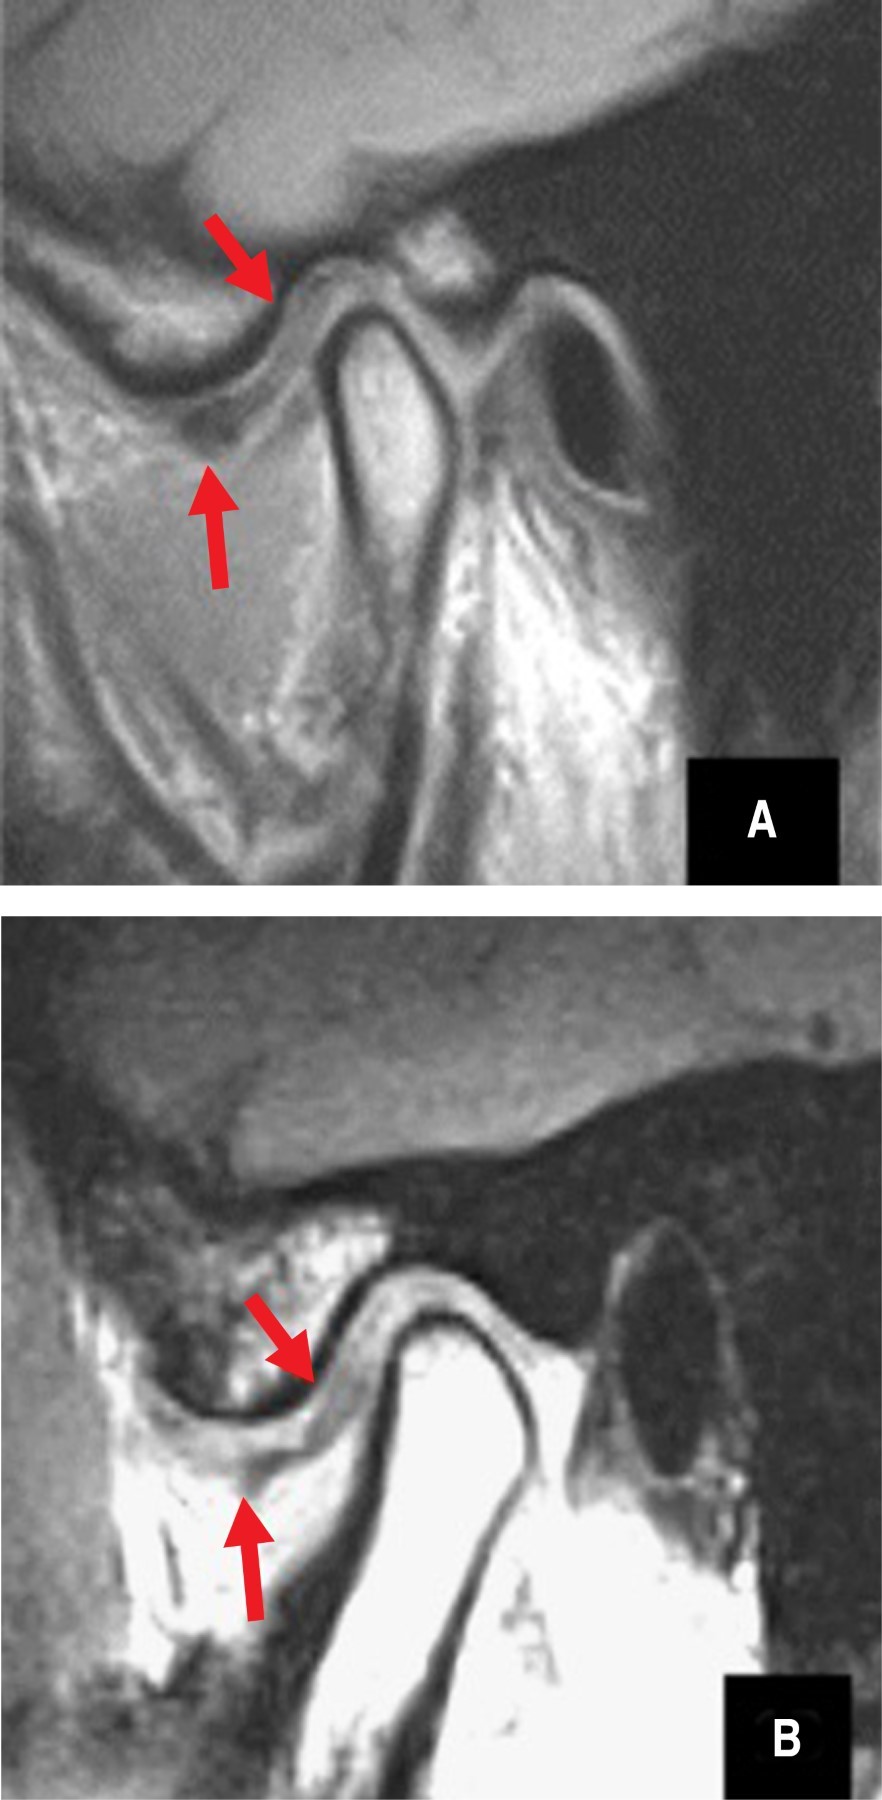

Figure 3